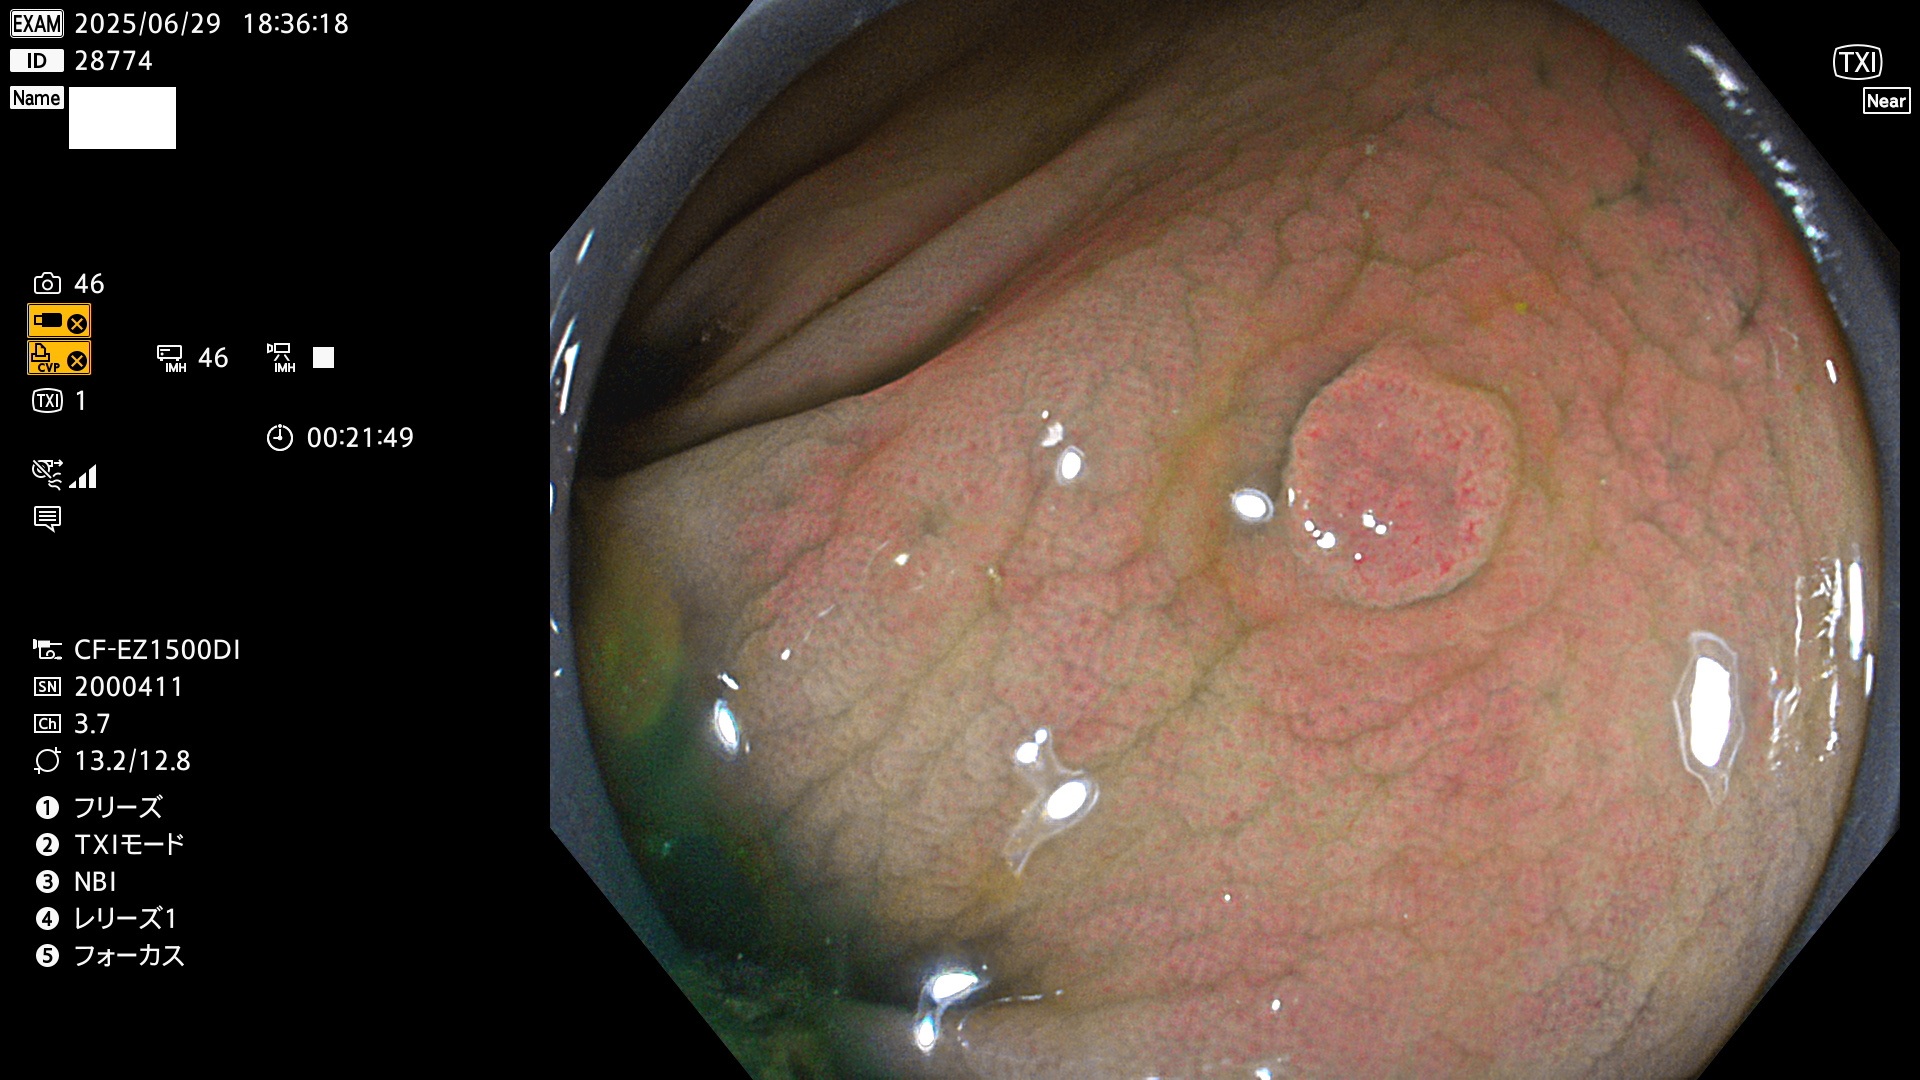

今週のUb、Uc型腺腫

完全に平坦な物をUb、陥凹している物をUcと呼びます。Ubは認識が困難で、Ucはびらん(炎症)と紛らわしいために見落とされやすく、「内視鏡後・大腸癌」の原因になります。

毎週の検査(木・金・土・日)に発見されたUb、Uc型・腺腫を、その週の日曜の夜にUPし1週間、提示します。

抽出の対象期間 2025年6月26日〜6月29日の4日間(40件の検査)7個 (7/40=18%)